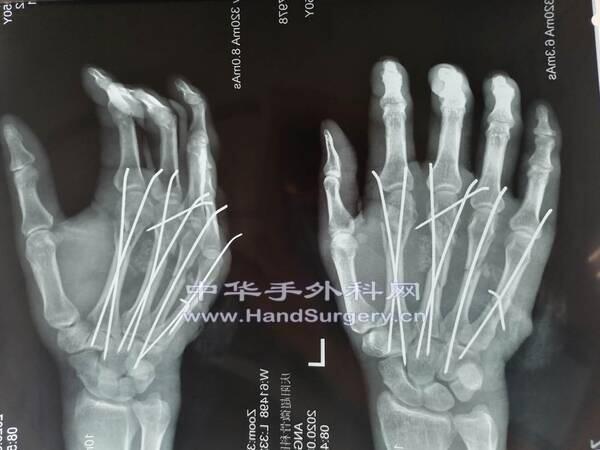

[手部外伤] 不看伤口 就几个克氏针

大家各提提意见

打针技术很棒

手感不错